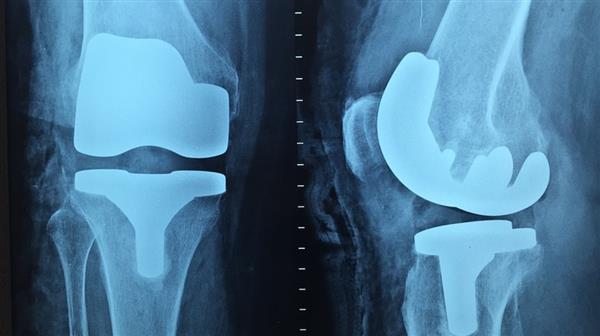

法国最近宣布的一项新的3D打印项目有可能改善世界各地千百万患有膝盖问题的人们的生活。这个名为FollowKnee的项目由法国国家研究机构(ANR)提供资金支持,并将借助3D打印技术,看到先进的假肢膝关节的发展。这项多学科合作项目资助了790万欧元的资金,可以在未来五年内彻底改革膝关节手术。

FollowKnee位于该国西北部的布雷斯特市,是一个“联合”这个词的多种意义上的共同努力,因为它涉及七个不同的组织和机构的参与,以及专注于开发替代品膝关节。膝盖是身体的一部分,一生中经受了很多的压力,越来越多的患者现在需要手术和修复术。在过去的二十年中,法国患者的假肢骨科膝关节数量增加了20%,这种趋势任然没有改变的迹象。该项目负责人Eric Strindel教授表示,医疗信息处理实验室(LaTIM),隶属于法国国家医学健康研究所(InSERM)。 “年轻的病人不再需要沉默地忍受痛苦,他们知道人工关节运作良好,可以运动,跑步或打高尔夫球,肥胖症正在恶化膝关节,你的体重数越高代表着更大的压力重量在膝盖上,会导致磨损和撕裂。

最初,在该计划的头三年,由FollowKnee的外科医生团队安装了220个3D打印假肢膝关节。他们还将安装大约30个专用传感器,这些专用传感器用于追踪假体的状况并检测出任何问题。由法国原子能委员会法国格勒诺布尔制造,这些传感器将主要安装在年轻患者身上,因此可以长时间记录他们的表现。五年后,我们的目标是要有一个市场化的产品并获得临床认证。 Imascap将负责营销工作,以及创建3D模型和维护相关的数据库。